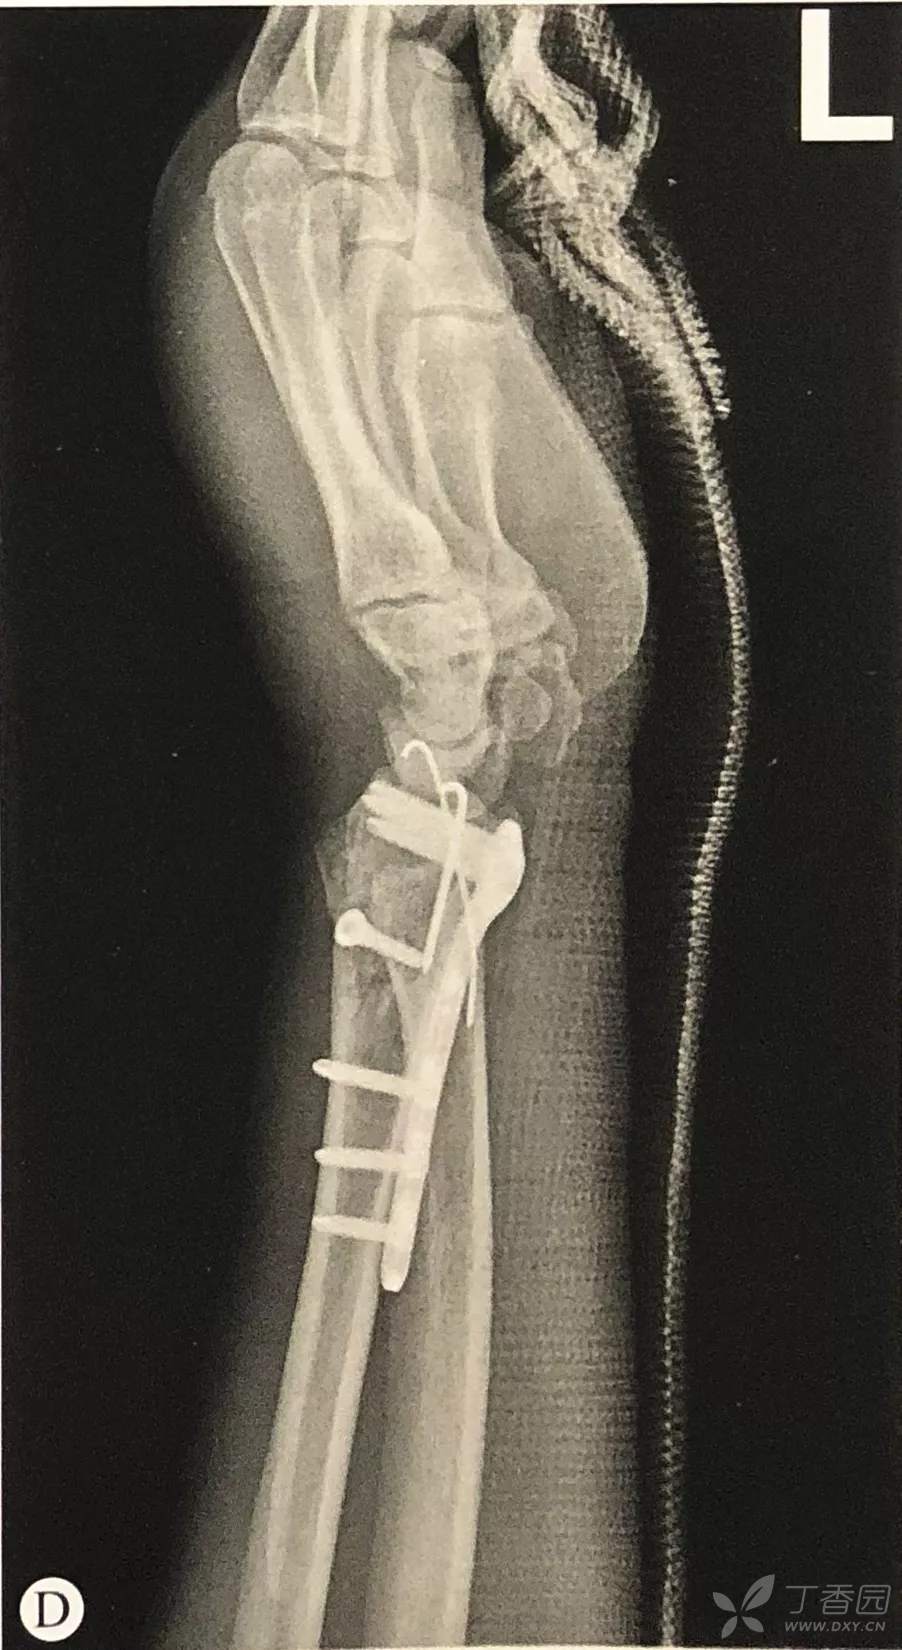

桡骨远端骨折手术技巧:切开复位内固定术

- 钢板应尽量靠近关节面放置,以使远端螺钉位于软骨下骨内,提供良好的力学支撑,对于骨质疏松患者,这点尤为重要;

- 通过钢板钉孔平行于桡骨远端关节面钻入一枚克氏针,尽量贴近软骨下骨,透视下确认位置;

- 平行于该克氏针置入1枚锁定螺钉,注意此时钢板偏离桡骨干的角度,即为通过此技术可以恢复的掌倾角的角度;

- 腕关节尺偏20°透视检查螺钉位置,避免螺钉进入关节;

- 至少置入2枚远端锁定螺钉,去除克氏针;

- 通过下压钢板贴附于桡骨骨干纠正背侧成角畸形;

- 置入剩余的螺钉完成最终的固定。

桡侧钢板远端螺钉位置:

McQueen等的研究表明,桡骨远端背侧皮质较薄,而关节面下的软骨较为致密,因此钢板应贴近桡骨远端从而使螺钉向背侧远端,使螺钉固定于软骨下骨而非置于背侧皮质。